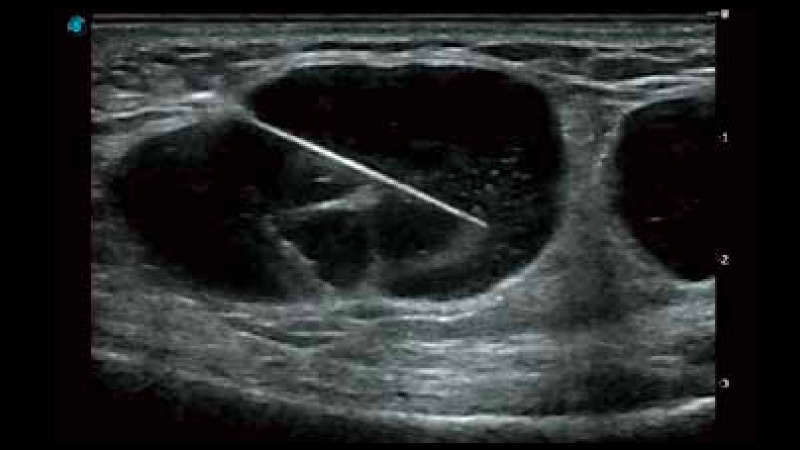

穿刺增强